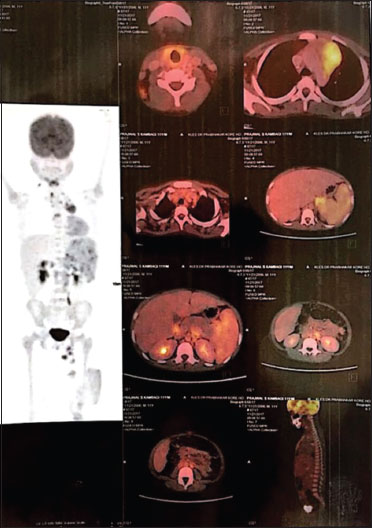

| Figure. 1 Baseline positron emission tomography–computed tomography

In addition to supportive care including packed red cell transfusion, the patient was started on chemotherapy as per German protocol, consisting of two cycles of vincristine, etoposide, prednisolone, and adriamycin and four cycles of cyclophosphamide, Vincristine, prednisolone, and dacarbazine. A dramatic improvement in symptoms, with a quick rise in hemoglobin levels, and disappearing evidence of hemolysis were noticed after the first cycle of chemotherapy. After two cycles of chemotherapy, the PET-CT showed complete metabolic response with a Deauville score of 1. He further completed four cycles of chemotherapy and continues to be in remission for the past 2 years. The child has gained 8 kg of weight in the past 2 years, fever and hepatosplenomegaly have subsided, and the child has never required blood transfusion again. His current hemoglobin is 12.2 g/dL. Repeat PET scan 3 months back revealed no FDG uptake in lymph nodes or spleen. The child is asymptomatic and on regular follow-up.